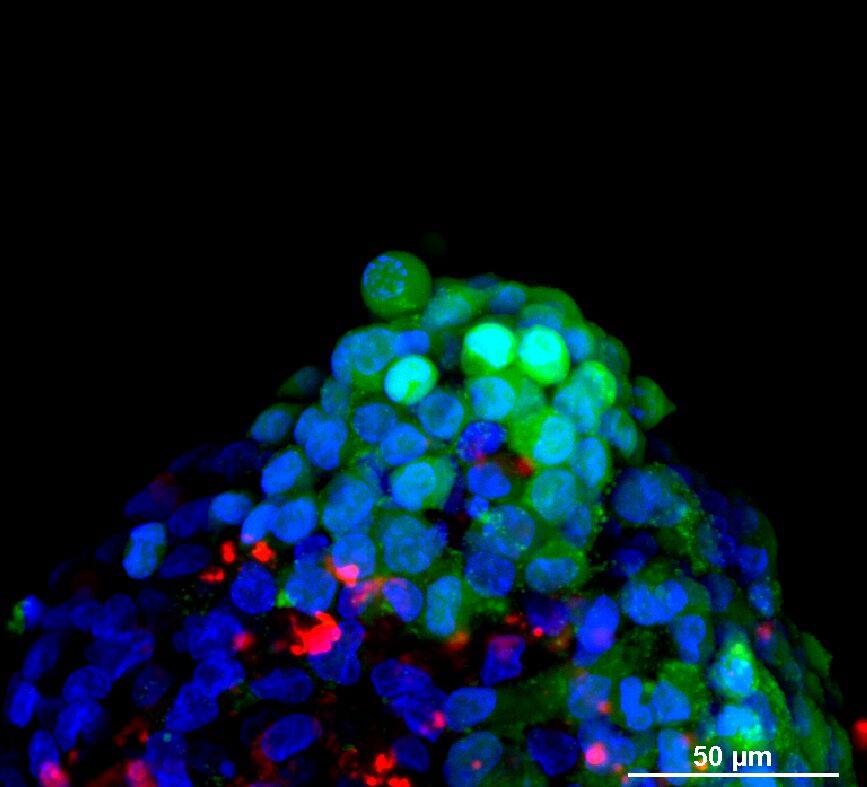

为了生成 3D 球体,将 NCI-H460 细胞(源自非小细胞肺癌)以两种不同的密度接种在超低吸附培养板中:3×103 个细胞/孔或 700 个细胞/孔。在直径分别达到约 400-500 或 150-200 um 后,用细胞毒素剂处理球体 6 天。通过使用钙黄绿素 AM 和碘化丙啶 (PI) 的活/死染色来观察和评估药物的效果。钙黄绿素 AM 是一种细胞渗透性染料,用于测定细胞活性。非荧光钙黄绿素 AM 在活细胞中被细胞内酯酶水解后转化为(绿色)荧光钙黄绿素。PI 是一种红色荧光核染色剂,通常用于检测死亡细胞,因为它不能进入完整的活细胞。最后,使用 Hoechst 染料将细胞核染成蓝色。

我们采用 CrestOptics X-Light V3 转盘共聚焦结合 Prime BSI 相机(Photometrics,像素尺寸 6.5 um)进行采集。我们比较了使用 20 倍空气物镜(CFI Plan Apo Lambda,尼康,0.7 NA 和 1mm WD)和 25 倍硅油物镜(CFI Plan Apo Lambda S,尼康,1.05 NA 和 0.55 mm WD)进行的采集。在图 A 中,我们展示了从总共 150 um 的 Z 堆栈中获得的最大强度投影 (MIP) 图像;特别是,使用 20 倍空气物镜和 25 倍硅油物镜获得了相同的球体。图 B 显示了使用两种物镜获得的 3D 球体同一区域的放大。

使用 20 倍空气物镜和使用 25 倍硅油物镜获得的图像之间的比较(图 A、B 和 C)突出了基于生物应用的透镜选择的重要性。从 20 倍到 25 倍的转换导致分辨率提高(基于 25 倍的 NA 大于 20 倍 NA),这当然会影响图像质量,并且还会导致光折射减少。事实上,浸油通过用更高折射率的介质代替透镜和盖玻片之间的空气间隙,大大提高了显微镜的分辨率,从而减少了光的折射。

在 3D 成像中,样品的折射率与其浸没介质的折射率相匹配对于深层组织观察至关重要。硅酮浸油非常适合透过厚厚的生物样本进行成像;它与细胞和封固剂的折射率非常吻合,与使用普通 20 倍空气物镜获得的图像相比,减少了球面像差,产生了更亮、分辨率更高的图像。

图 B:使用 20 倍空气物镜(左)和 25 倍硅胶物镜(右)获得的 3D 球体同一区域的放大。活细胞用钙黄绿素(绿色)标记,死细胞用 PI(红色)标记。细胞核用 Hoechst(蓝色)染色。这些图像是使用 CrestOptics X-Light V3 转盘获取的。